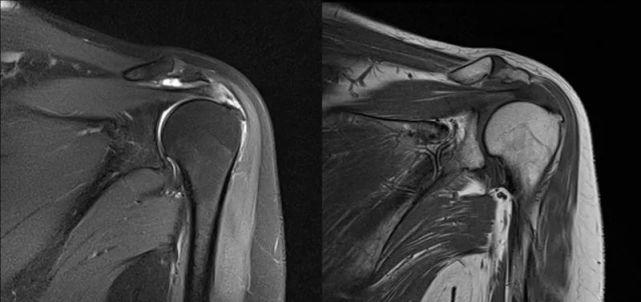

冈上肌肌腱撕裂核磁图,冈上肌肌腱损伤伴积液

肩关节矢状位mri:提示冈上肌腱连续性存在,前下盂唇损伤,前下关节囊

冈上肌mri目前是诊断肩袖疾病中最常用的检查,可以直观的观察肩袖肌腱